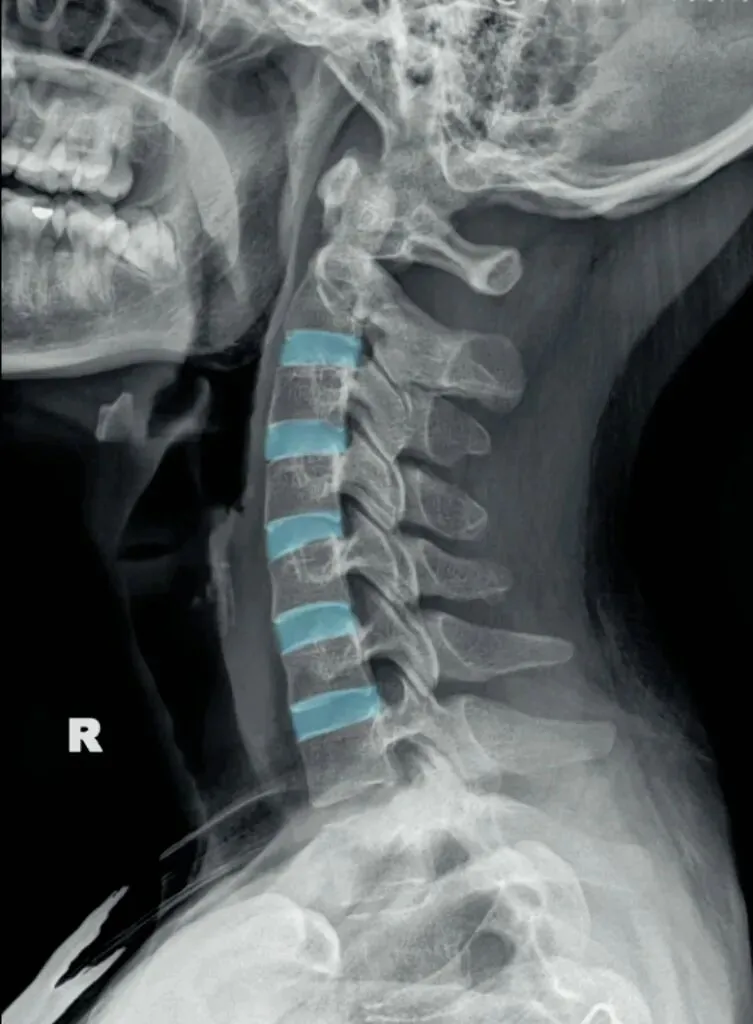

二弓指的是颈椎生理曲度,在颈椎侧位X线片中,正常生理状态下呈现向前凸出的弧形曲线,呈半C型前凸类似弓形,是人体脊柱生理曲度的重要组成部分。颈椎曲度变化能够反映颈椎整体功能的变化。

常见的颈椎曲度改变有曲度变直和曲度反曲。

颈椎生理曲度测量的方法多种多样,其中应用最广泛的测量方法是Borden法。从齿状突后上缘开始向下将每个椎体后缘相连成为一条弧线,然后从齿状突后上缘至C7椎体后下缘作一直线测量,两条线间最宽处的垂直横交线的距离即为颈椎生理曲度深度。

正常时,最宽处在C4椎体水平正常为12毫米,正负5毫米,小于7毫米为生理曲度变直,大于17毫米为生理曲度过度前屈,小于零时为生理曲度反曲。